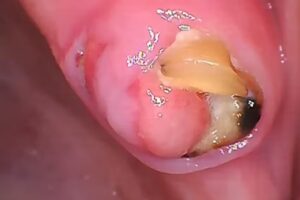

El consultorio parece estar enfocado principalmente en la odontología general, con tratamientos habituales como obturaciones, limpiezas, control de caries y solución de urgencias. Para las personas que buscan una consulta dental de rutina, este tipo de práctica suele ser suficiente para mantener la salud bucal al día. No es una clínica grande con múltiples especialistas, sino un espacio más pequeño donde la atención es más directa y personalizada.

Desde el punto de vista del equipamiento, el consultorio ofrece lo necesario para la atención dental cotidiana: sillón odontológico, instrumental básico, materiales para restauraciones y elementos de higiene y desinfección. No obstante, no se trata de una clínica de alta tecnología enfocada en la última generación de equipos digitales, escáneres intraorales o sistemas complejos de diagnóstico por imagen. Para la mayoría de las necesidades diarias de salud bucal esto no es un problema, pero quien busque procedimientos muy sofisticados deberá evaluar si es el entorno adecuado.